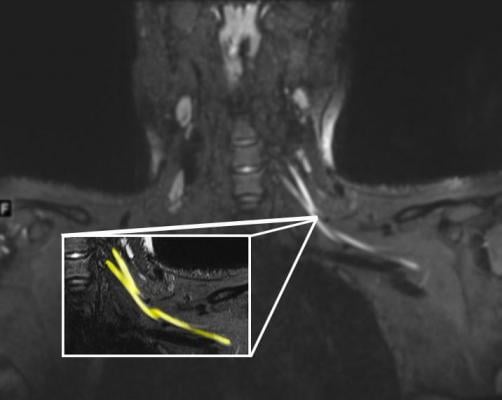

An MR image of a patient in their early 20s shows nerve injury (highlighted in yellow) of the left brachial plexus in the neck. The patient experienced left arm weakness and pain after recovering from COVID-19 respiratory illness, which prompted them to see their primary care physician. As a result of the MRI findings, the patient was referred to the COVID-19 neurology clinic for treatment. Image courtesy of Northwestern University

"Let's say you have numbness in your fingers. That might actually be due to problems in your neck, elbow or wrist, and the best way to figure it out is with an MRI or ultrasound," said lead author Swati Deshmukh, M.D., assistant professor of radiology at Northwestern University Feinberg School of Medicine and a Northwestern Medicine radiologist. "We offer advanced imaging that shows even really, really small nerves, which helps us localize where the problem is, assess the severity and suggest what might be causing it."

The imaging described in the paper includes ultra-high-resolution ultrasound and MR neurography (MRI of peripheral nerves, which impact the arms and legs). They can help localize where a patient's problem is, show the severity of nerve damage, how many nerves are affected and if the nerve damage also has impacted the muscles.